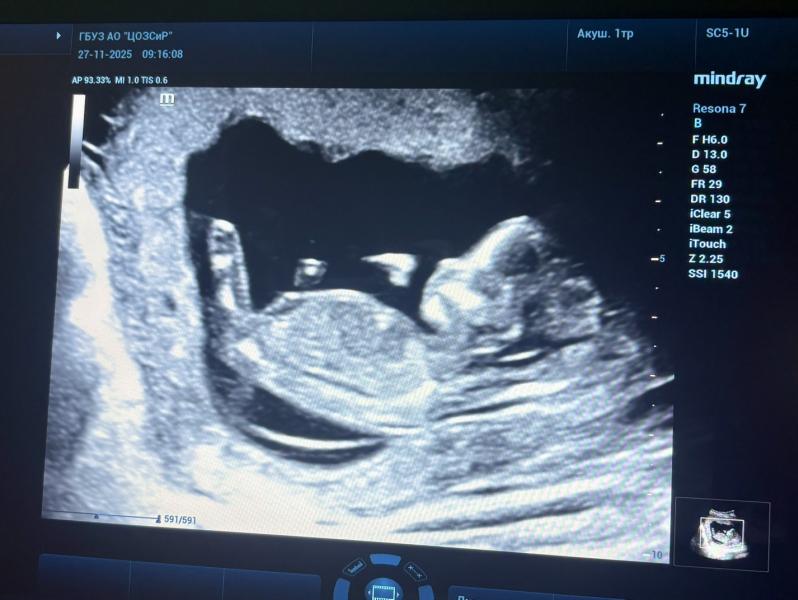

Мальчик